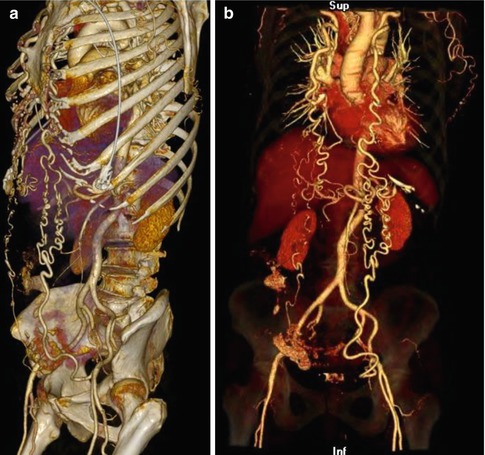

Fig. 5.7

(a) Direct volume rendering (DVR) technique in a patient with aortic coarctation clearly providing the anatomical details. (b) Direct volume rendering (DVR) technique in a patient with aortic coarctation: The opacity of the bone dense Hounsfield units is reduced displaying them transparent, leading to an excellent visualization of the vascular structures